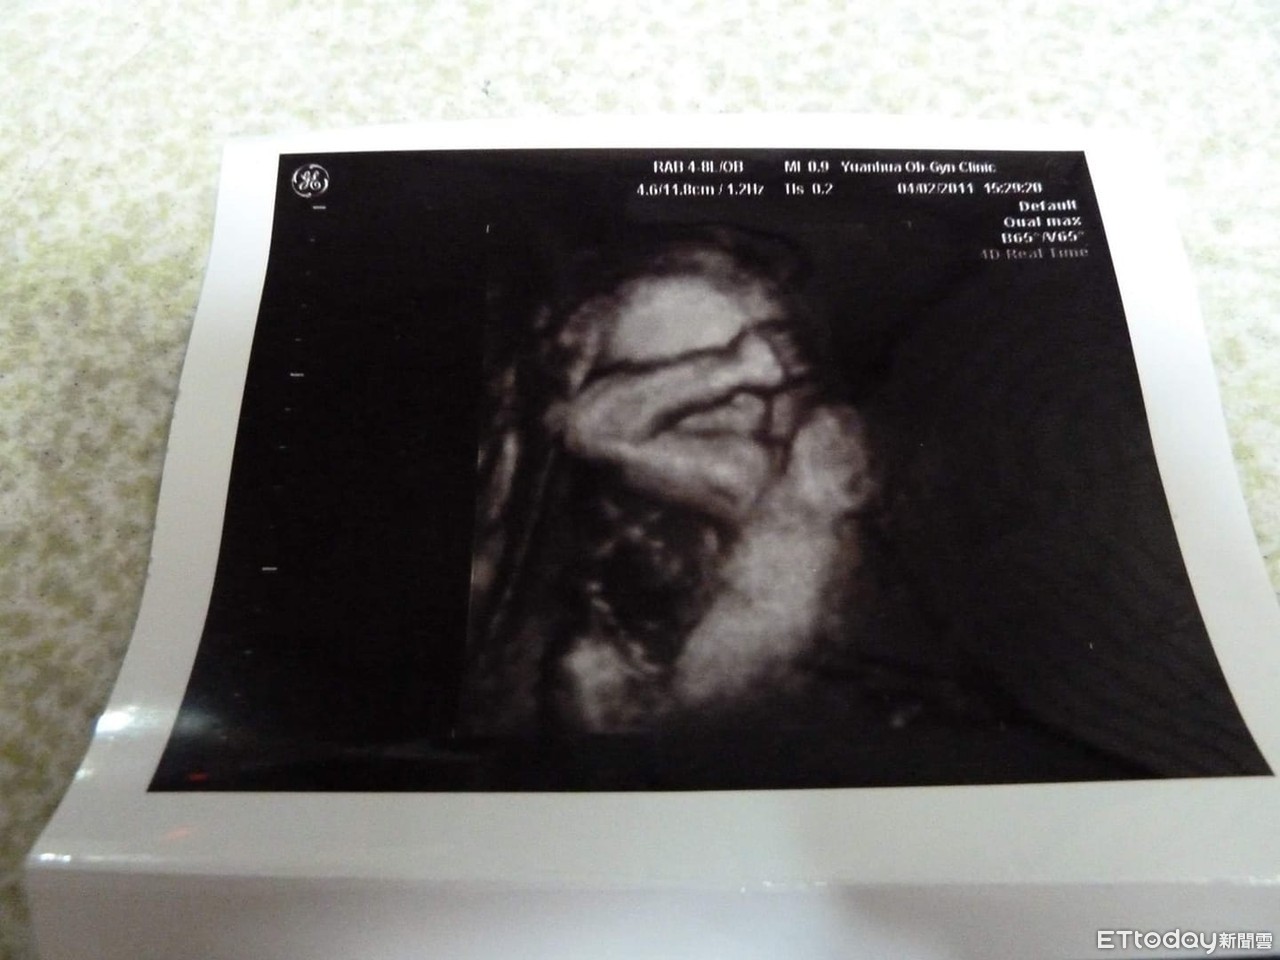

▲兒子在媽媽肚子裡做仰臥起坐!(圖/張魯酥提供,請勿隨意翻拍,以免侵權。)

打從娘胎就開始健身?一名爸爸透露,最近心血來潮翻出兒子的超音波照片,結果兒子早在娘胎裡就立志保家衛國,竟手抱頭做起「仰臥起坐」,讓他看得哭笑不得。而照片引發關注,網友見到寶寶的體態,紛紛驚呼「這麼小就秀肌肉!」

一名男網友在臉書《爆廢1公社》趣味分享一張傳家寶等級的「超音波照片」,他回憶10年前,當時老婆辛苦懷胎7個月,恰好當時夫妻倆在軍職單位服務,而好動的兒子彷彿軍人魂上身,竟在媽媽肚子裡做起「仰臥起坐」!

照片可見,寶寶手抱頭,身體微彎曲,真的就像正在做仰臥起坐,張爸爸向《ETtoday新聞雲》笑稱,轉眼間兒子「元元」已經是10歲的小男孩了,可惜孩子沒有胎內記憶,不過可遺傳到媽媽的數學好基因,從小數學天賦驚人,「大班去考全國數學MPM大賽,沒有補習就拿全國第7。」

照片曝光後,引發網友紛紛朝聖笑回,「這照片上的是手臂肌肉線條嗎」、「生出來是一名猛男」、「胎教就看莒光園地吧」、「胎兒版麒麟臂」、「所以這是他以後常用的睡姿嗎?我兒子拍片時的睡姿,出生後常出現」、「伏地挺身動作預備」、「所以他也算同梯的,誤」、「你錯了,他在青蛙跳」。張爸爸也在留言串回應,「現在是小肥宅,也許是傘兵跳」。